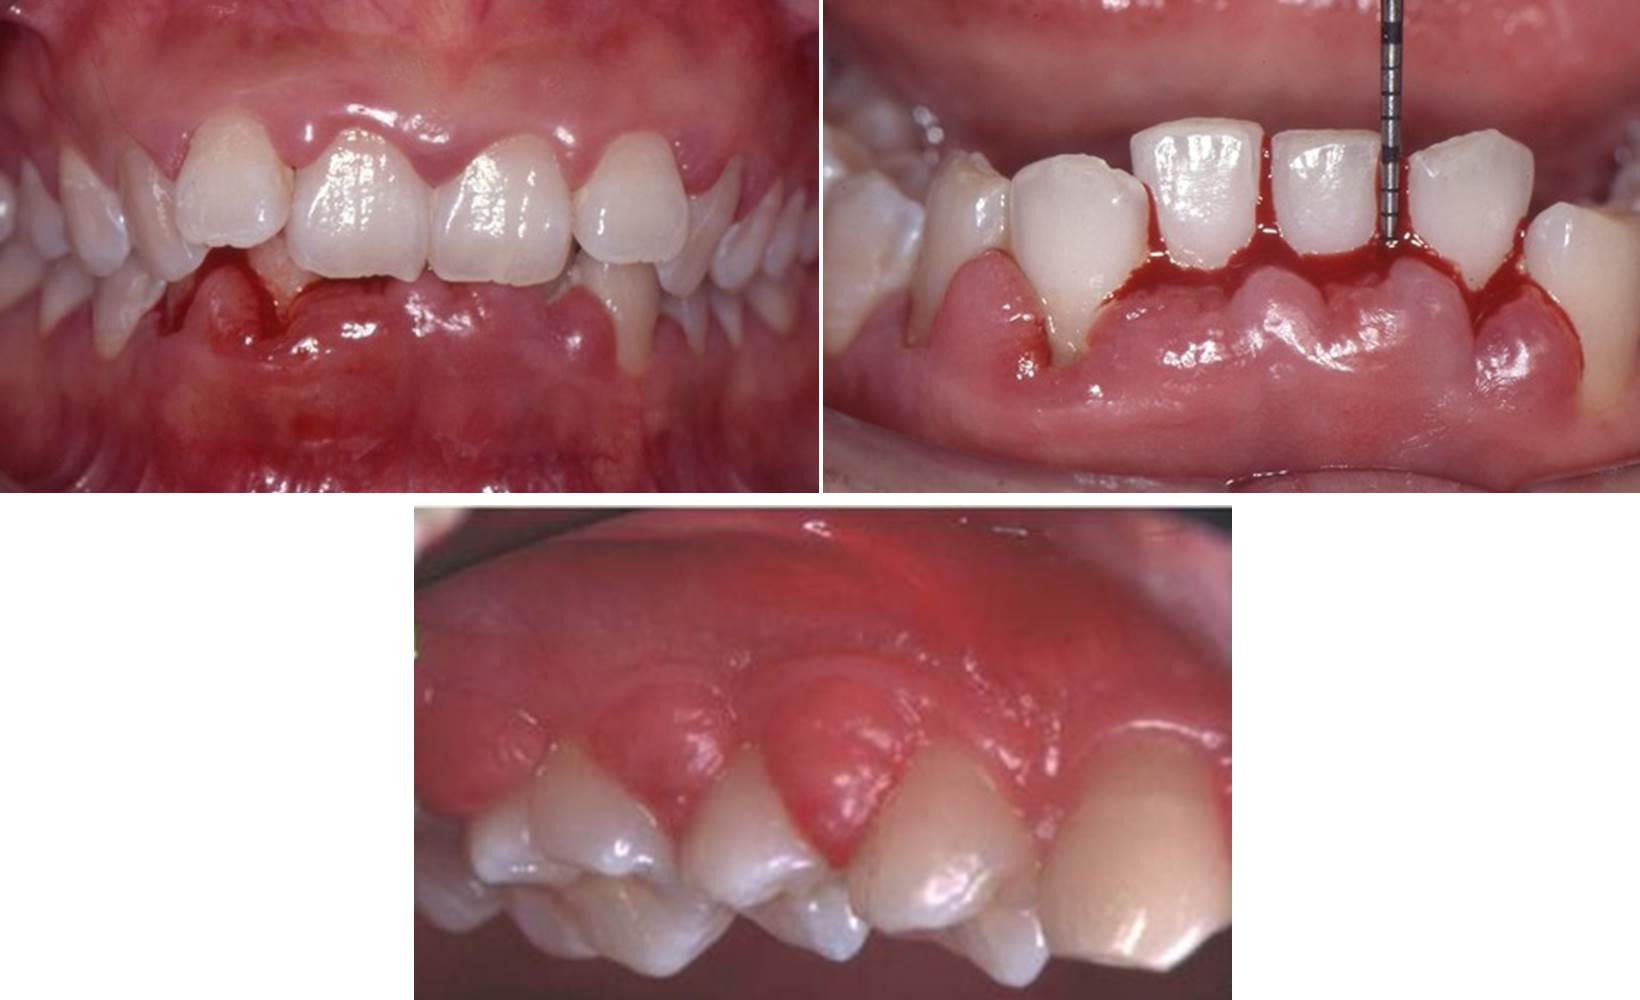

「歯茎が腫れている」という相談が多くなってきています。歯茎が腫れてしまう歯科的な原因は‟プラーク(歯垢)”と呼ばれる細菌性の因子が主ですが、例外的に、薬剤性に、特に高血圧症の方が服用するカルシウム拮抗成分の入った降圧剤(ニフェジピン等)の副作用歯肉増殖症が生じることがあります。

降圧剤を服用した人が皆、歯茎が腫れてしまうわけではありません。原因としては、「歯肉繊維中のコラーゲンの働きを阻害する」ことや、「カルシウム拮抗薬によって活性化された歯肉中の線維芽細胞が基質を多量に産生する」こととの関連が示唆されていますが、一番の原因はプラークの存在です。適切なブラッシングによりプラークコントロールが出来ていれば、薬を飲んでいても腫れは治まることが多いのです。

数年前は降圧剤の薬を変更してもらうことも多かったですが、最近では変更しなくても治るというデータも多く、必ずしも服用薬の変更をお医者さんに指示する必要はありません。 場合によっては、歯肉切除をしたり、抗生剤を服用することでも改善します。